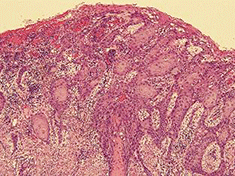

手術検体の病理組織所見では、びらん部に角化を伴う扁平上皮癌細胞の浸潤を認めたが顎骨浸潤はなく(図4)、頸部リンパ節に転移も認められなかった。最終診断は左側上顎高分化型扁平上皮癌(pT2N0M0)であり、現在、外来通院にて経過観察中である。

図❹ 病理組織写真(H-E染色×100)